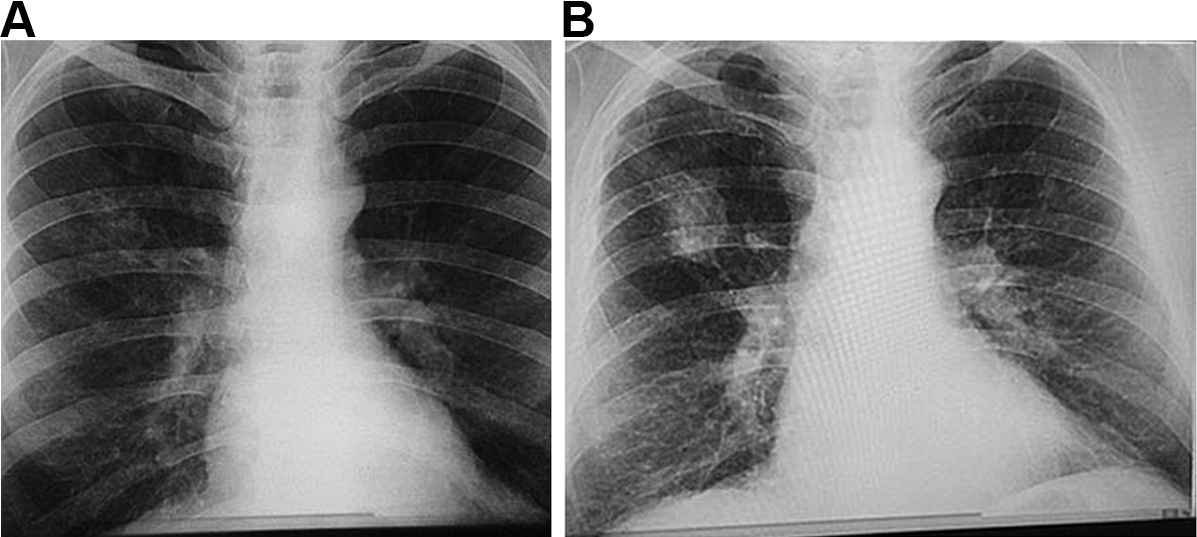

The manifestations of CWP can vary greatly between individuals, depending on the composition of the dust and duration of exposure, as well as host-related factors.34 Accumulation of dust occurs initially in the walls of the respiratory bronchioles, the adventitia of the blood vessels and the bronchoalveolar canals. Collections of dust-laden macrophages accumulate in the walls of the airways, particularly at their bifurcations, and in adjacent alveoli.1 Fibrous tissue is deposited, which later shrinks and leads to distortion of local lung structures.34 With increasing release of inflammatory mediators and deposition of fibrous tissue, these “macules” become larger and develop into more organised, dense, central, dust-pigmented lesions called micronodules,1 which can be palpated in the lung and seen on a chest x-ray (Box 1). Many larger rounded nodules then develop, particularly in the mid and upper zones of the lungs. Subsequently, centriacinar emphysema develops.35

Eventually, large masses of coal dust (Box 2), lymphocytes, dust-laden macrophages, reticulin and collagen may converge to form areas of PMF. These usually occur in the upper posterior parts of the lungs and appear as large rounded masses on the chest x-ray34 (Box 1, B). The presence of PMF represents “complicated” CWP and is associated with increasing symptoms and mortality.34

Box 1 – Chest x-rays of a coal worker (A) showing background nodulation and early progressive massive fibrosis (PMF) in the right upper zone, and (B) 12 years later, showing PMF